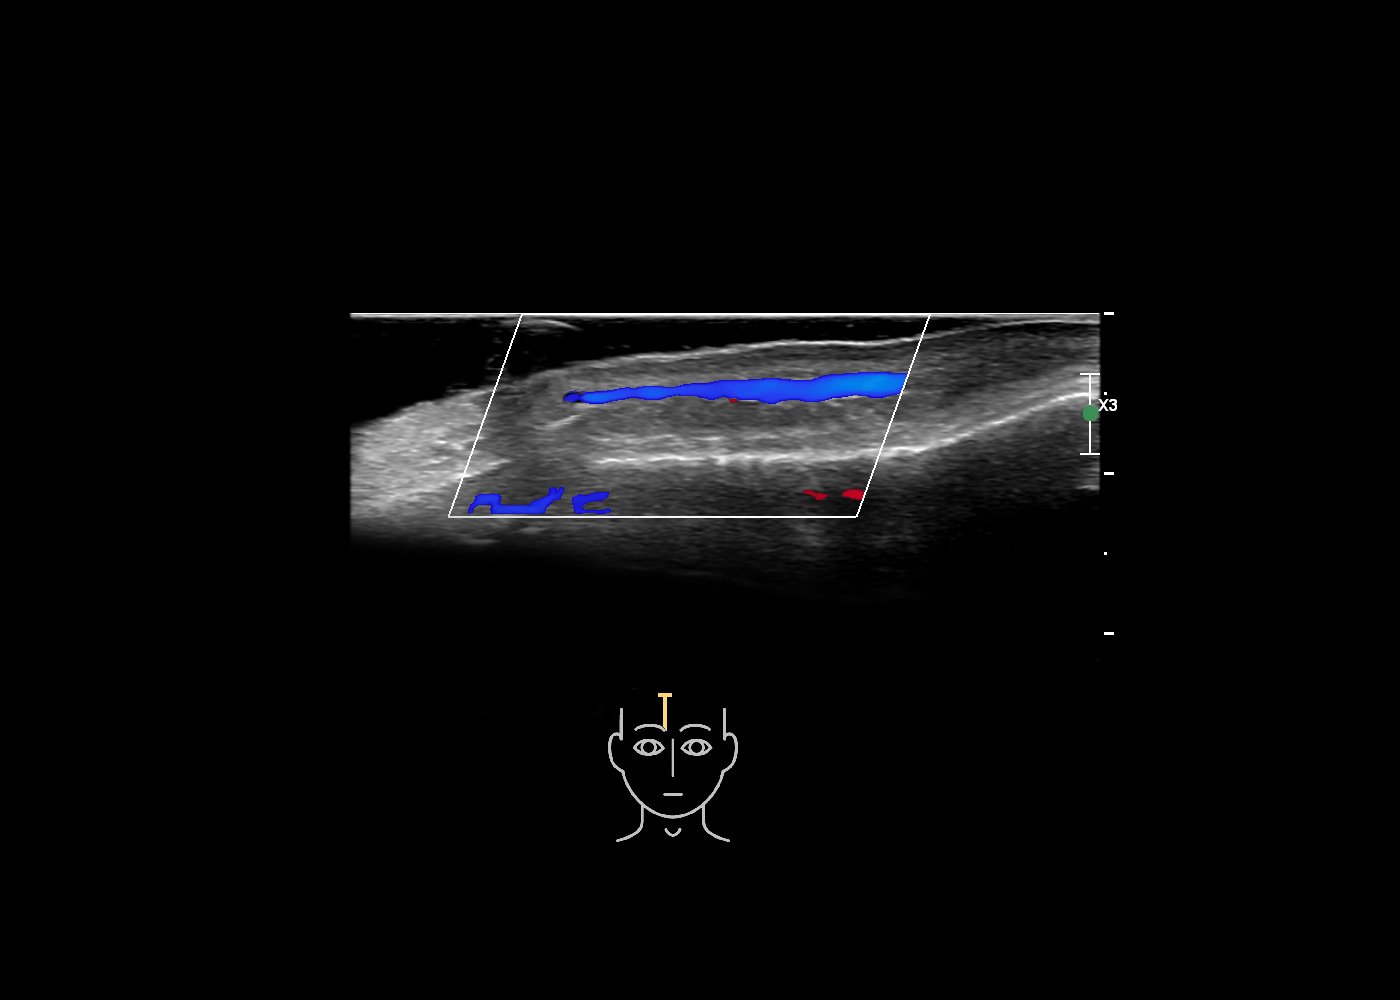

In this section you will learn more about the different layers of the face with the use of ultrasound. When you click on the secondary ultrasound image, you will see the different structures as an overlay. This will help to train yourself to recognize the different layers of the face.

Study the first image to recognize the different layers. If you are sure about the layers, swipe to the second image to view the answer (if applicable).